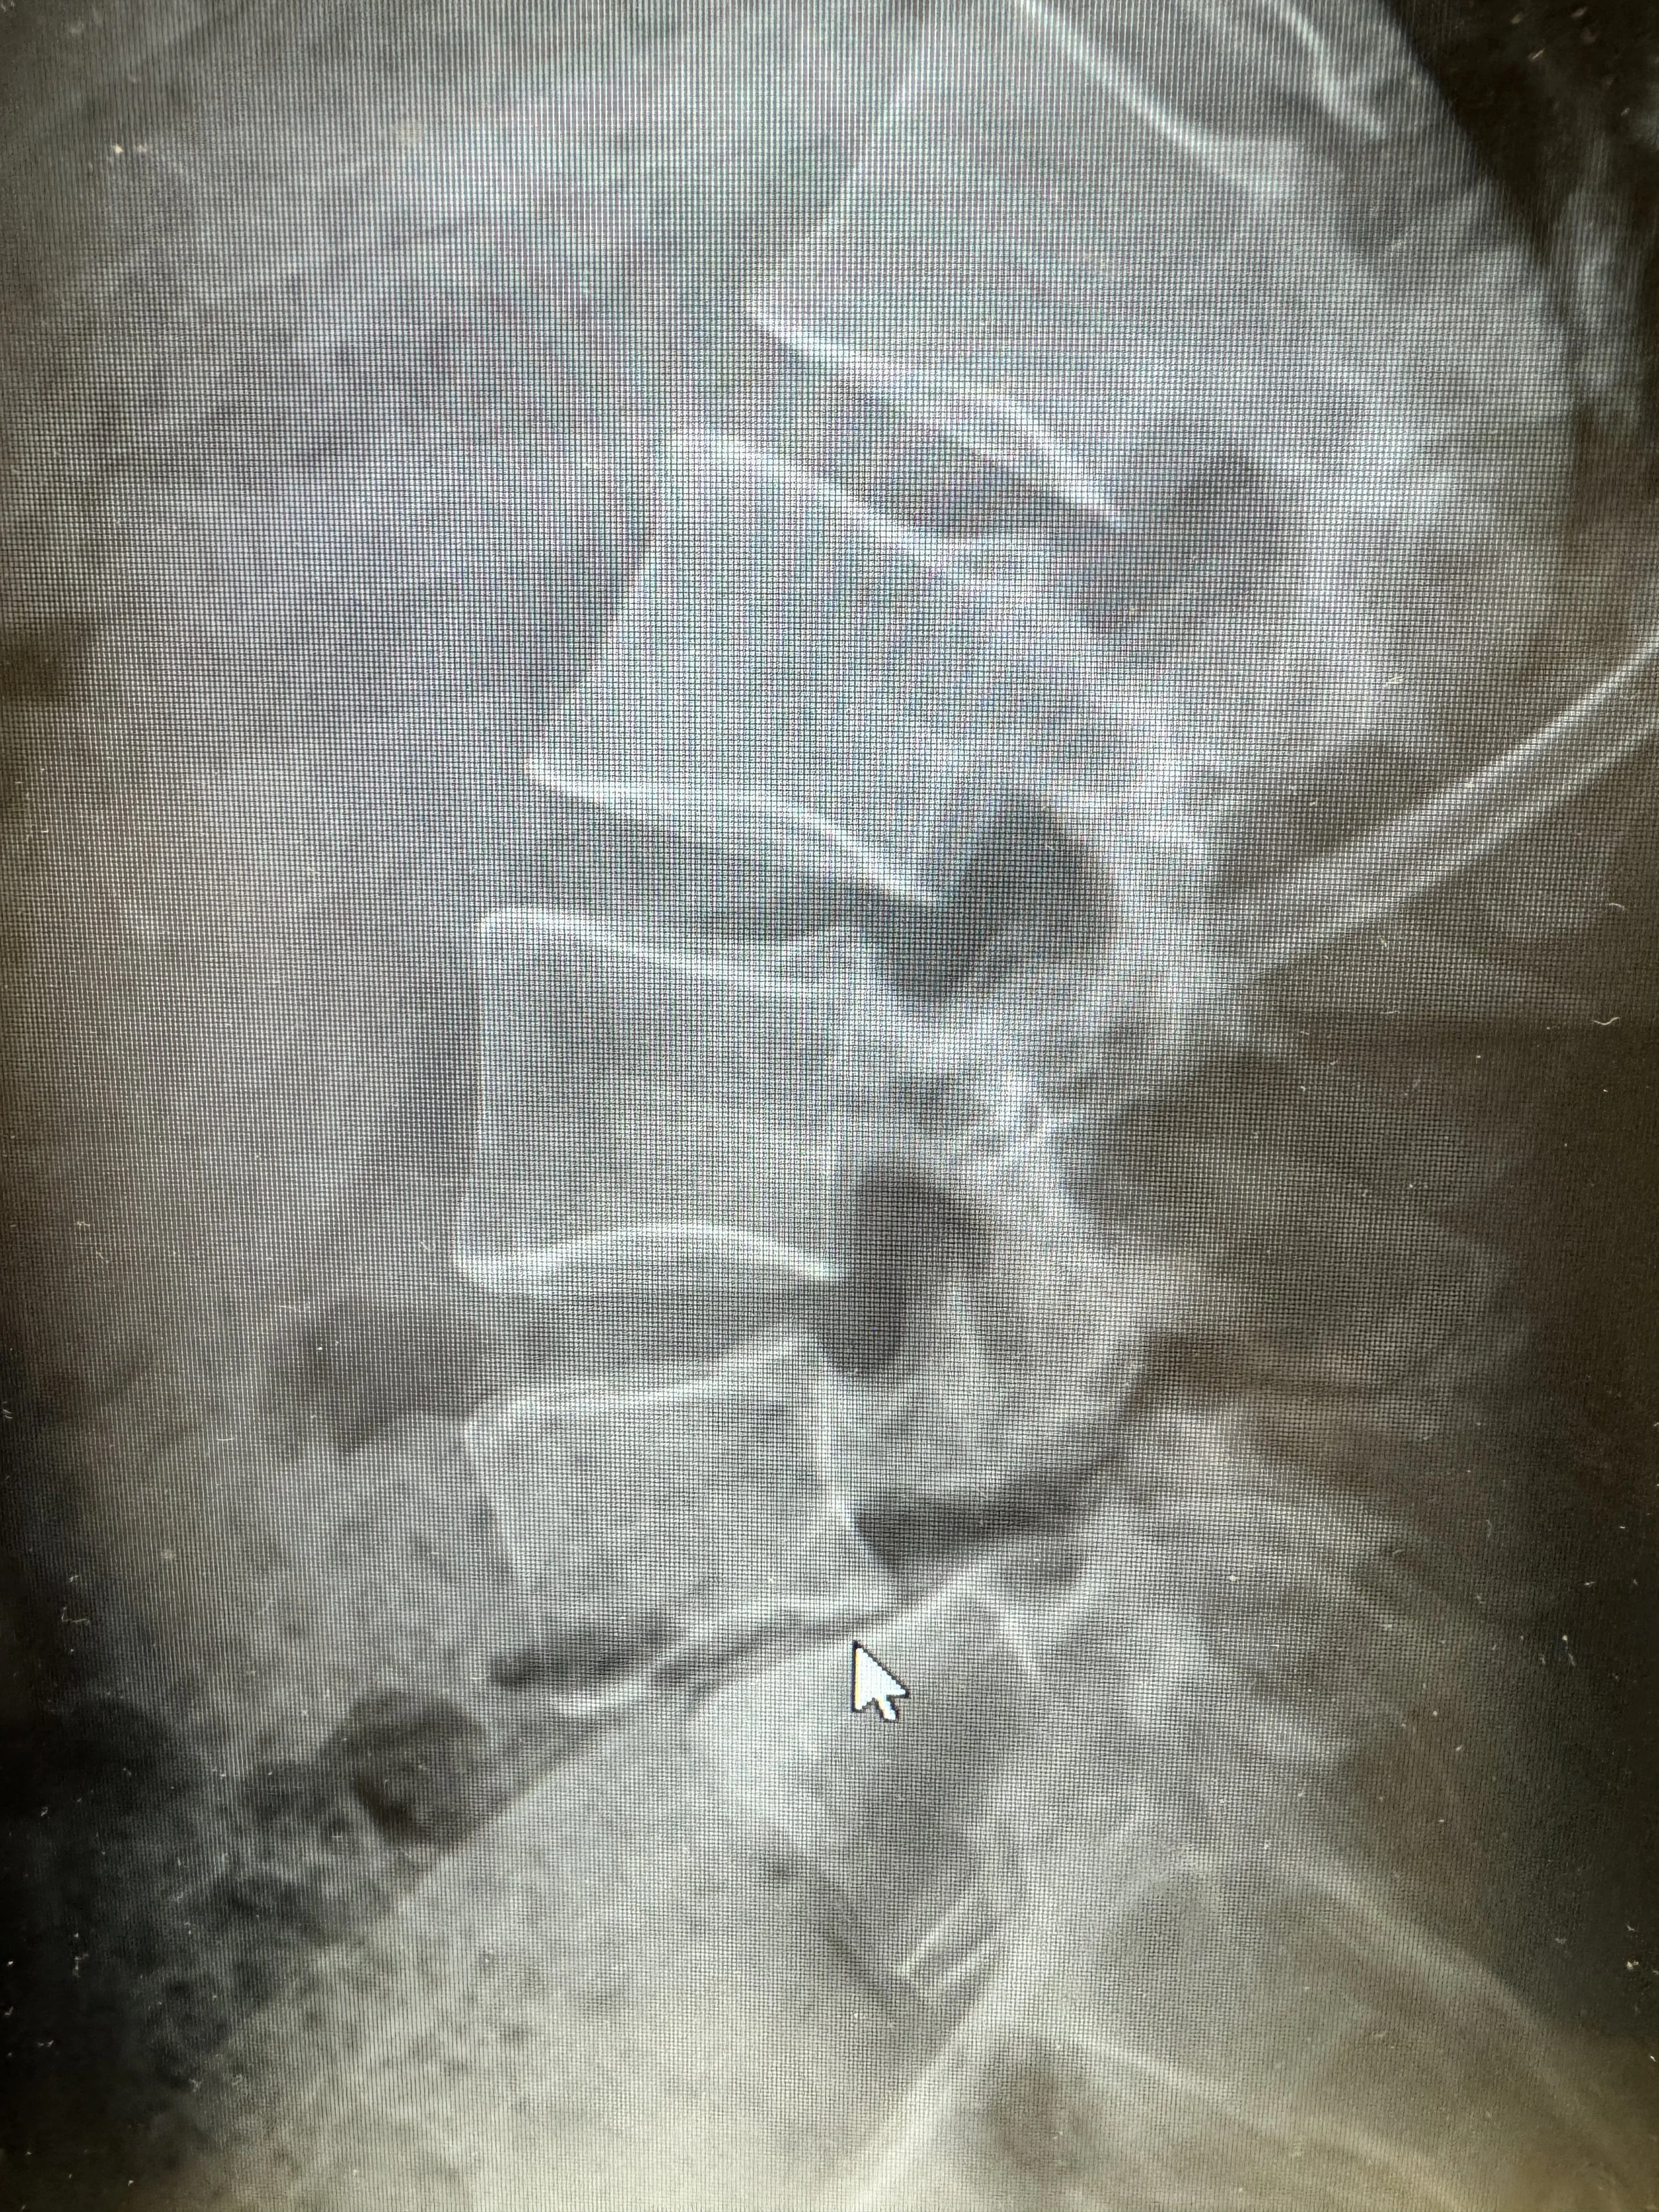

All in the L4-L5…

Unstable Grade 2 spondylolithesis

Severe disc degeneration

Bilateral pars defect (fractures of the facet joints)

Spondylolysis is movement and misalignment of vertebrae. My L4 and L5 are naturally off by 9mm just standing. When I lean forward it shifts to nearly 15mm off and when I bend backwards it’s 3mm off. This movement without a disc creates bone on bone rubbing.